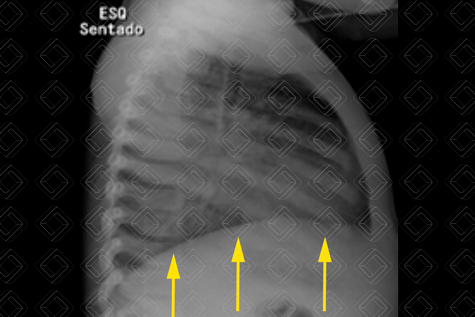

Texto alternativo para a imagem Figura 2. Créditos: Dra. Elazir Mota - Rio de Janeiro/RJ

Descrição das figuras 1 e 2: Na radiografia de tórax AP observa-se uma opacidade que apaga o contorno cardíaco à esquerda (seta verde) e o diafragma esquerdo (setas vermelhas). No estudo em perfil, evidencia-se somente um diafragma (setas amarelas). Fica a dúvida se há somente pneumonia ou pneumonia associada a derrame. O próximo passo na população pediátrica é fazer uma ultrassonografia de tórax.

• Radiografia de tórax AP ou PA + perfil: Exame de escolha na população pediátrica, mas, diante da suspeita de derrame pleural, idealmente deve ser complementado com a ultrassonografia do tórax (lembrando que a avaliação de derrame pleural com a incidência radiográfica em Laurell - decúbito lateral com raios horizontais - está em desuso);